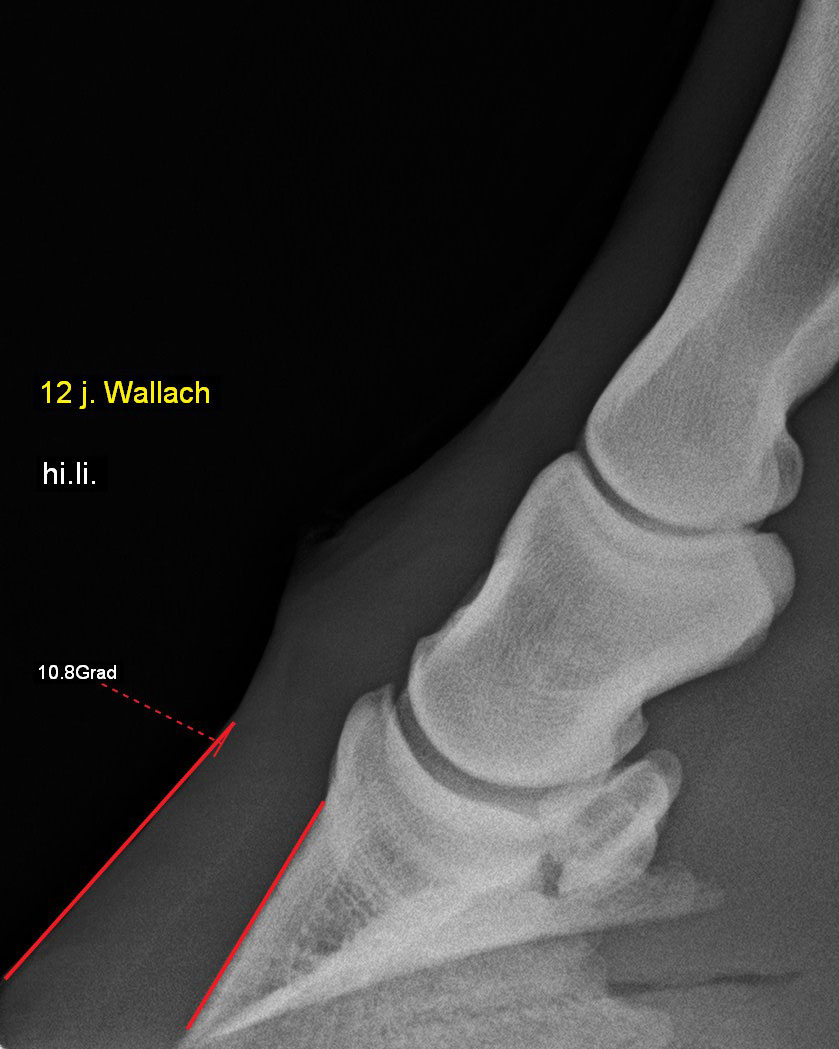

Zehe - 90°-Aufnahme

Hufrehe mit einer Hufbeinrotation von 10,8 Grad